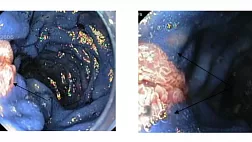

Эндоцитоскопия является одним из наиболее интенсивно развивающихся методов эндоскопической диагностики, позволяющим исследовать слизистую оболочку, а, по данным ряда экспериментальных работ — строму и паренхиму различных органов, с увеличением изображения до 1100 раз.

• По разрешающей способности с ней может сравниться только конфокальная лазерная эндомикроскопия, обеспечивающая увеличение до 1000 раз.

• Преимуществом эндоцитоскопии над конфокальной лазерной эндомикроскопией является отсутствие необходимости внутривенного введения флуорофоров.

• Витальные красители, наносимые топически на слизистую оболочку, свободно доступны и безопасны.

• С появлением в ближайшем будущем новых эндоцитоскопов для исследования пищевода, желудка, толстой кишки и дыхательных путей можно ожидать значительного увеличения точности эндоскопической диагностики ранних форм рака и предраковых заболеваний вышеописанных органов.

• Уже в настоящее время, с нарастанием увеличения изображения, обеспечиваемого эндоскопической аппаратурой, наблюдается тенденция смещения традиционной эндоскопической диагностики в сторону морфологического исследования и для эффективного выполнения эндоцитоскопии врачу-эндоскописту, безусловно, необходимо изучать тканевое и клеточное строение стенки органов желудочно-кишечного тракта и дыхательных путей.